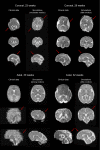

Accurate characterization of in utero human brain maturation is critical as it involves complex and interconnected structural and functional processes that may influence health later in life. Magnetic resonance imaging is a powerful tool to investigate equivocal neurological patterns during fetal development. However, the number of acquisitions of satisfactory quality available in this cohort of sensitive subjects remains scarce, thus hindering the validation of advanced image processing techniques. Numerical phantoms can mitigate these limitations by providing a controlled environment with a known ground truth. In this work, we present FaBiAN, an open-source Fetal Brain magnetic resonance Acquisition Numerical phantom that simulates clinical T2-weighted fast spin echo sequences of the fetal brain. This unique tool is based on a general, flexible and realistic setup that includes stochastic fetal movements, thus providing images of the fetal brain throughout maturation comparable to clinical acquisitions. We demonstrate its value to evaluate the robustness and optimize the accuracy of an algorithm for super-resolution fetal brain magnetic resonance imaging from simulated motion-corrupted 2D low-resolution series compared to a synthetic high-resolution reference volume. We also show that the images generated can complement clinical datasets to support data-intensive deep learning methods for fetal brain tissue segmentation.